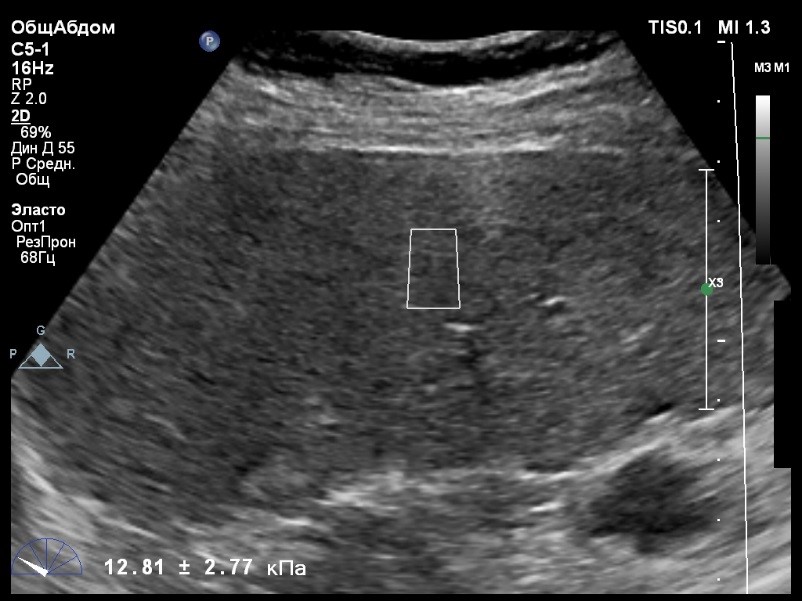

Предыдущее исследование было выполнено с помощью транзиентной эластографии, получена медиана жесткости 16,9 кРа (13,8-22,8). На момент настоящего исследования, пациент не принимал пищу на протяжении 4 часов, АСТ, АЛТ не превышают патологических значений.

Пациент обратился к доктору с направлением на исследование степени жесткости печени.

В виду технических сложностей выполнения исследования (избыточная масса тела), для оценки жесткости была выбрана технология компании Philips ElastPQ (точечная эластография) и прибор компании Philips Epiq 7. Исследование было проведено в соответствии с клиническими рекомендациями для ультразвуковых приборов компании Philips. В результате исследования были получены следующие результаты:

| 1 [16.86] kPa | 2 [15.14] kPa | 3 [12.83] kPa |

| 4 [12.81] kPa | 5 [13.07] kPa | 6 [15.01] kPa |

| 7 [16.95] kPa | 8 [14.06] kPa | |

Стандартное Отклонение [1.62] kPa Медиана Жесткости [14.54] kPa Фактор Качества IQR/Med 12%

Зона интереса расположена на более чем на один сантиметр глубже капсулы, параллельно ходу луча, в середине изображения, в участке печени лишенном артефактов

Капсула видна как яркая белая линия перпендикулярная ходу ультразвукового луча.

Стандартное отклонение (3,94 kPA) не превышает 30 процентов от полученного значения (15,01 kPA).

Для интерпретации полученных клинических данных были использованы Рекомендации по проведению эластографии сдвиговой волной для оценки жесткости печени при использовании ультразвуковых аппаратов компании Филипс с примером протокола. Стоит отметить, что для проведения исследования у технически сложного пациента был выбран аппарат экспертного класса. Подготовка пациента соответствовала проводимому исследованию. Представленные слайды проведенного исследования свидетельствуют о правильном техническом исполнении проб, что позволяет заключиться о достоверности полученных измерений. Таким образом, учитывая полученную медиану жесткости на уровне 14,54 кРа (12.83-16.95 kPa) и уровень стандартных отклонений не превышающих 30%, полагаю, что уровень степени фиброза соответствует стадии F4. Заведующий отделением УЗД МЦ «Асклепий», Глушенко Д. Е.